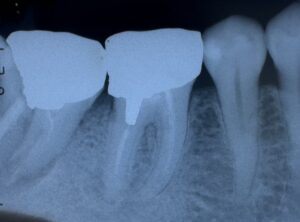

術前

第2大臼歯 は 歯根破折 して います

から

抜歯 しました。

第1大臼歯。

コレは 根管治療 と 歯内治療外科手術 が 必要 ですね!

近心根

特に

頬側側 の 根に 大きな トラブル が ある ようです。

1枚 の レントゲン がら

いろんな こと

読み取れ ます。